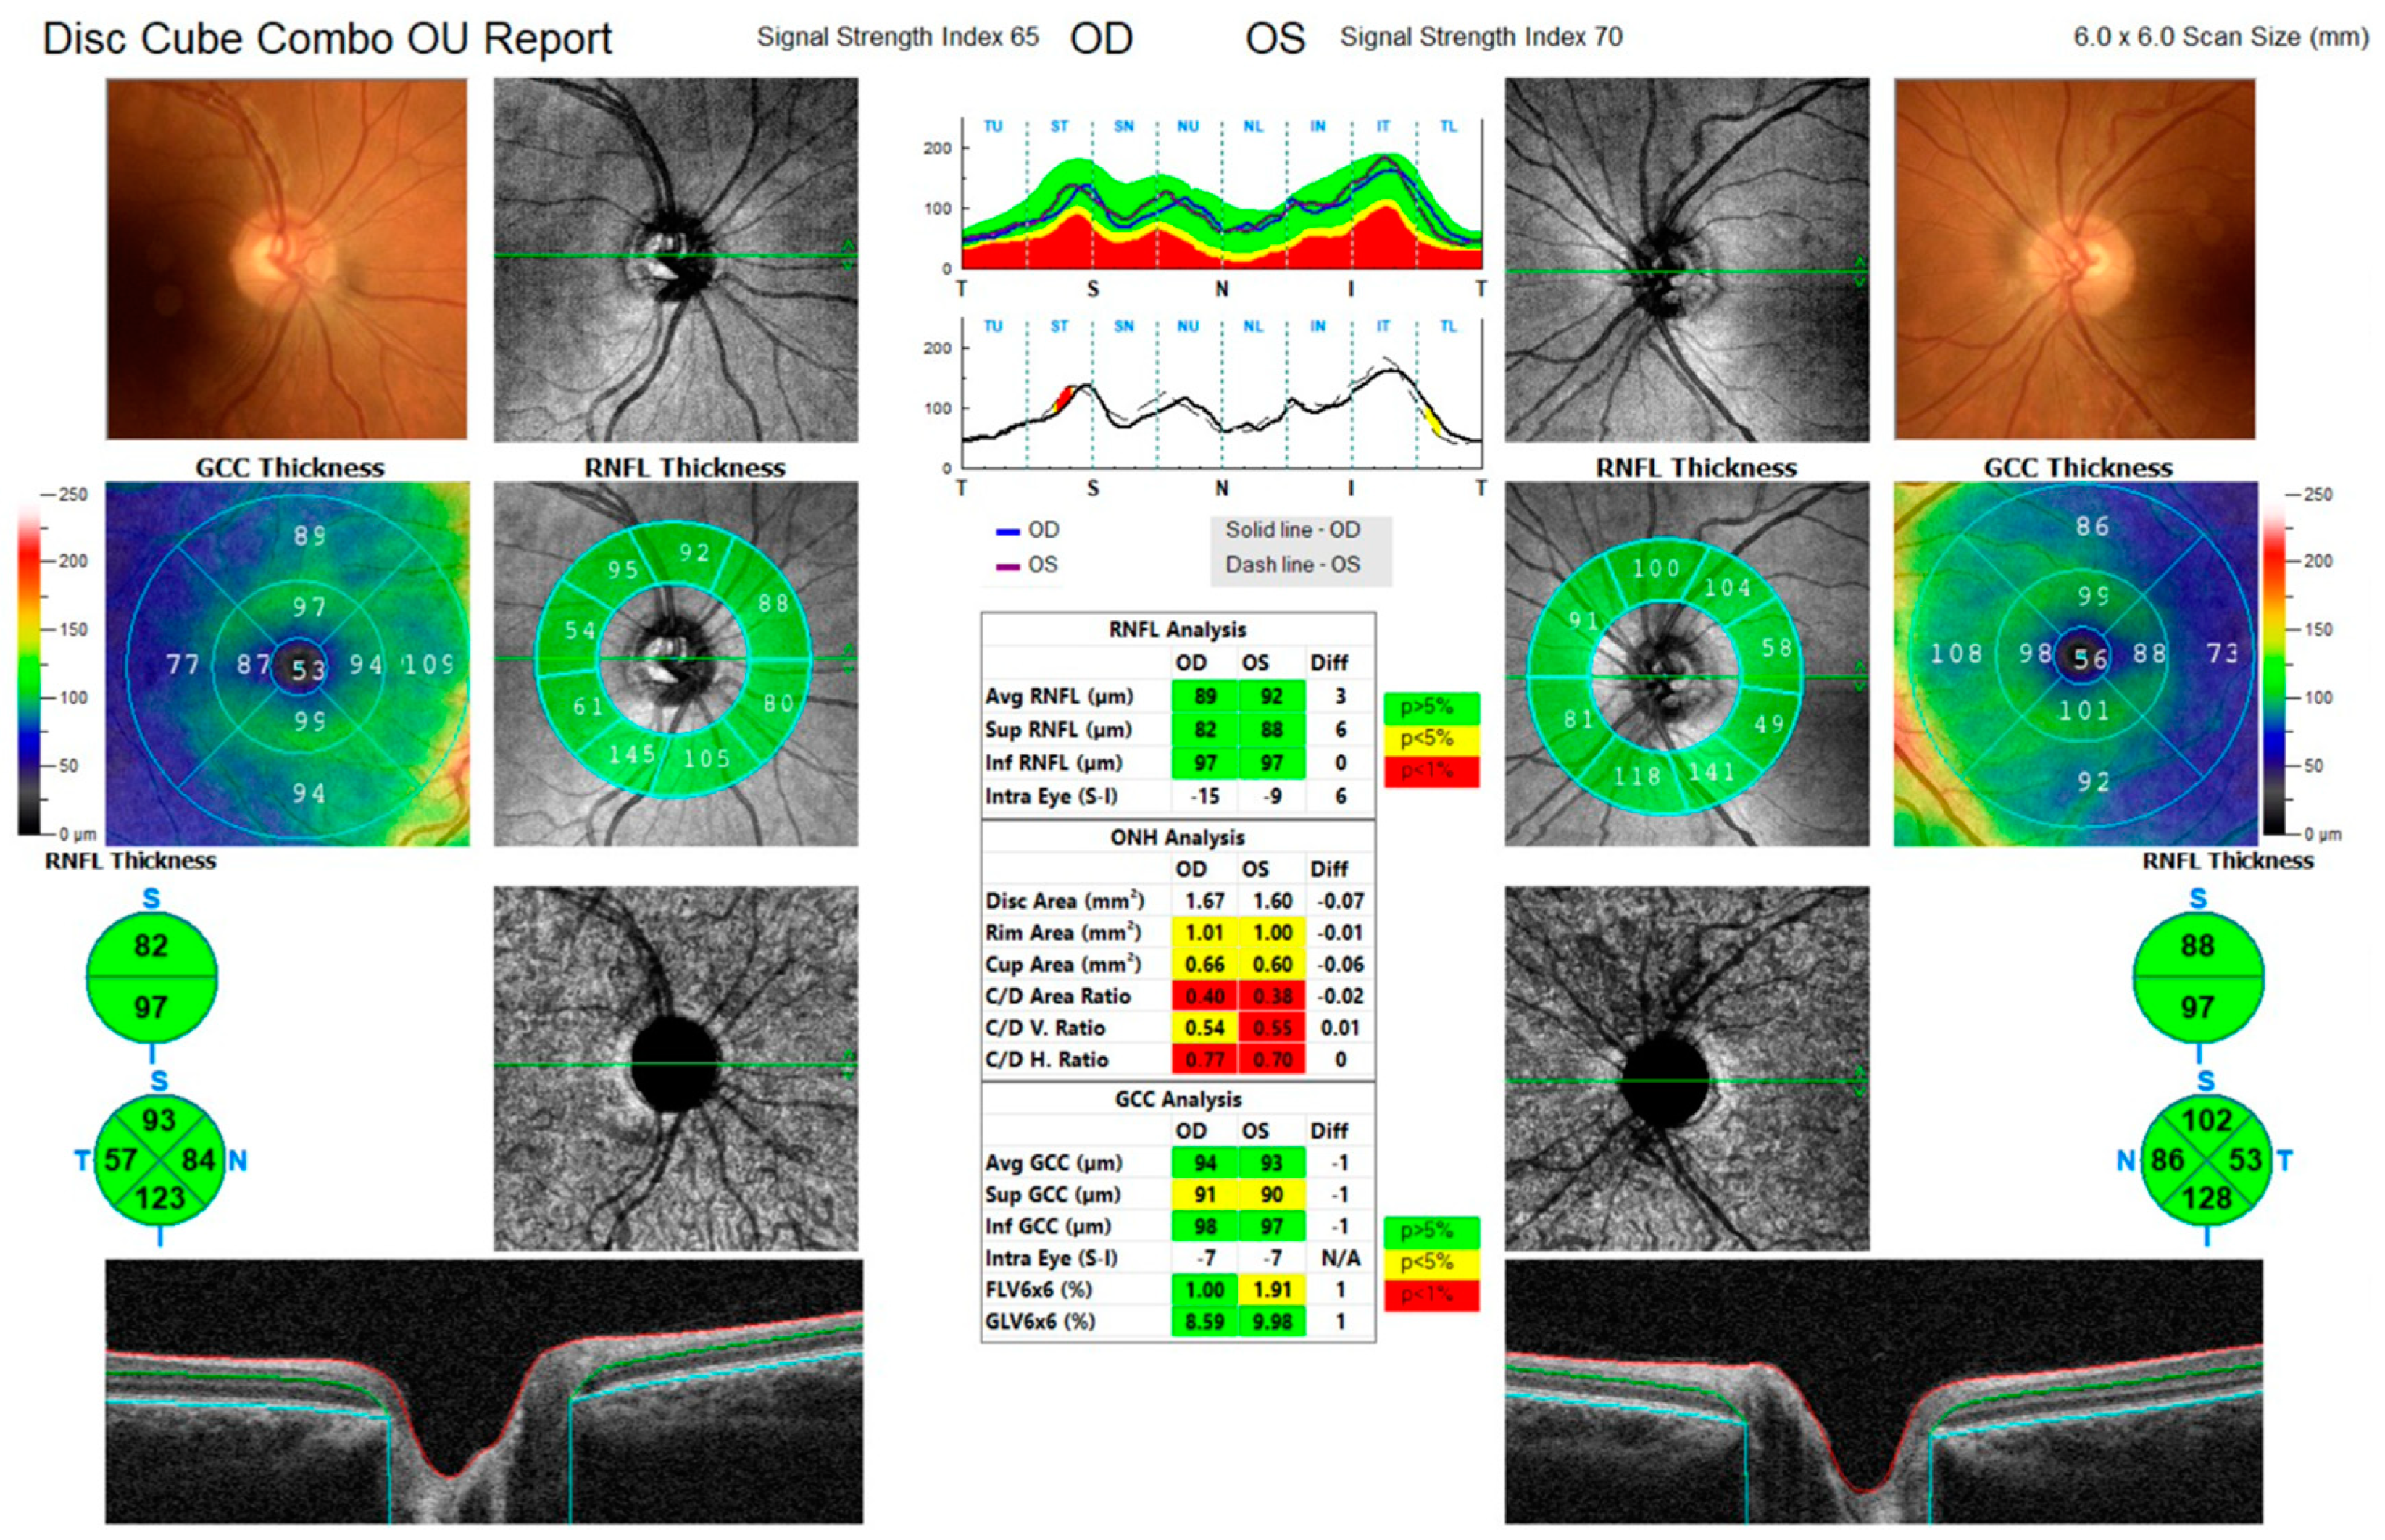

3. Case Series

3.1. Case 1

3.2. Case 2

3.3. Case 3